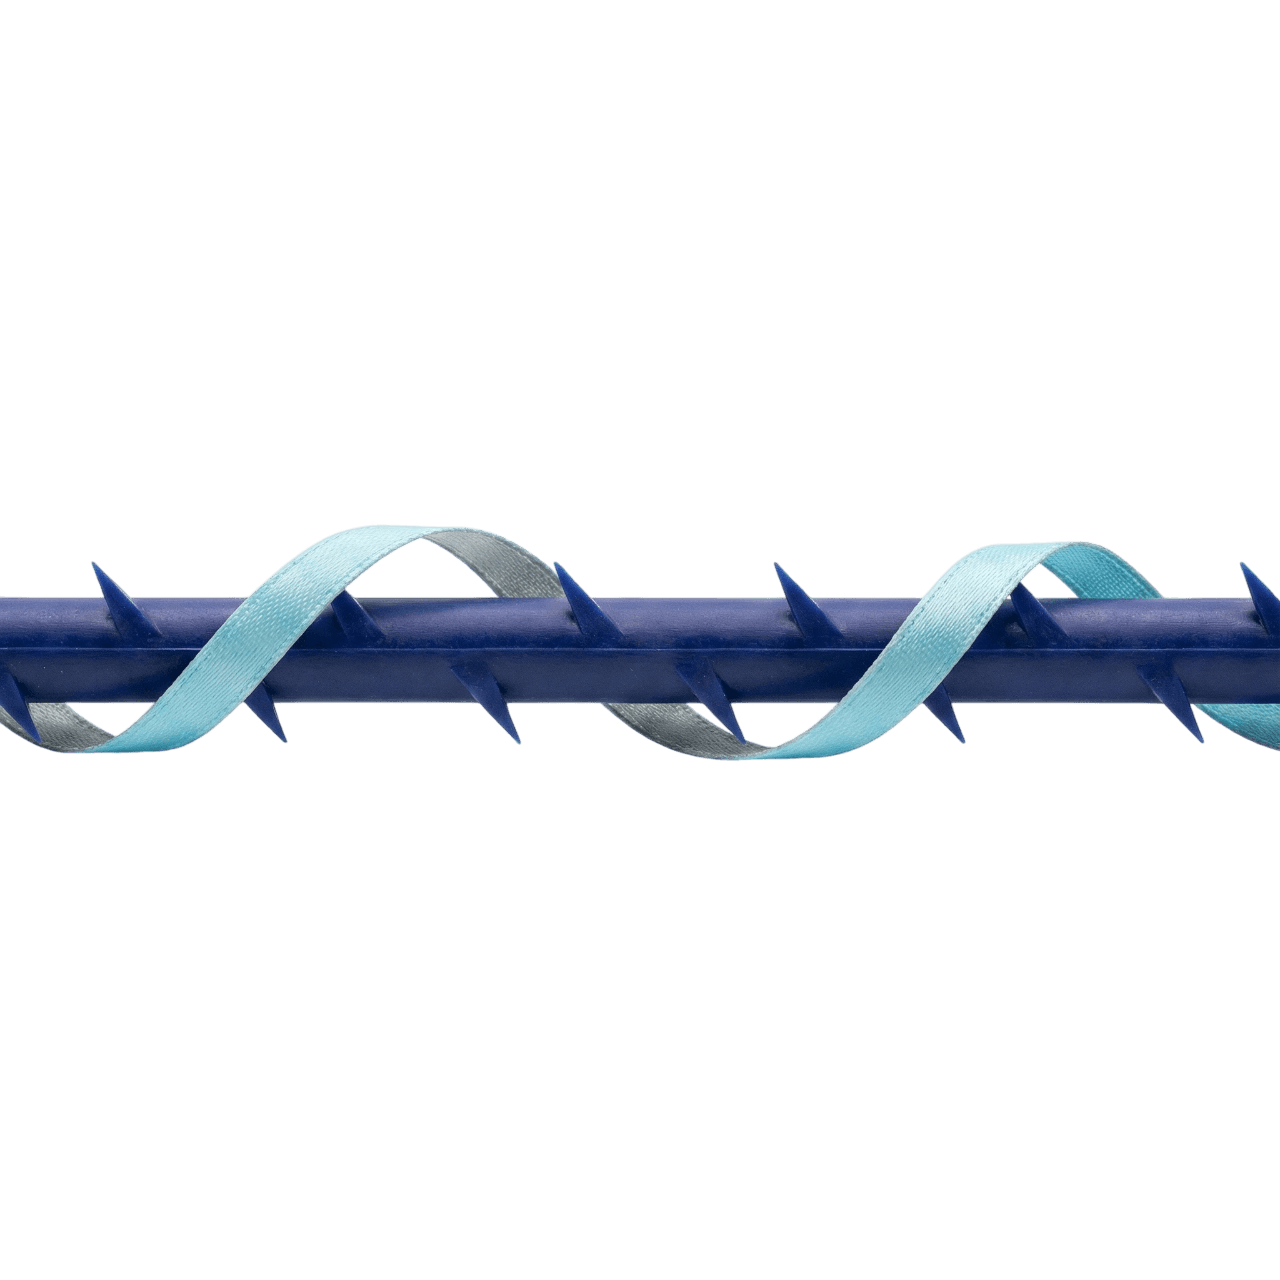

Technology, Principle, Core

Core Technology

Core technology and principles